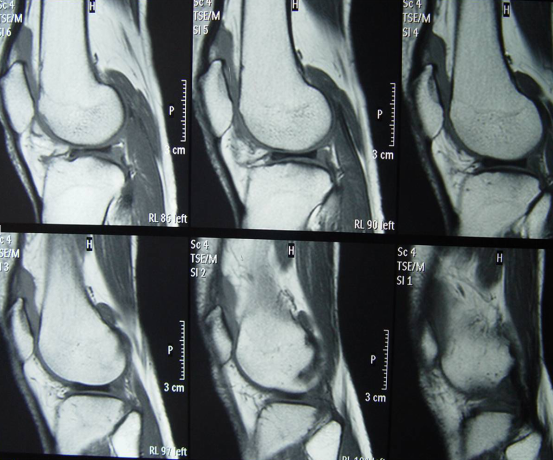

盤狀半月板的MRI特征

半月板厚大于15mm為絕對的征象

連續(xù)3個層面顯示前后角相連

兩個層面5mm以上的領(lǐng)結(jié)狀、高度相同的

半月板增厚增寬向內(nèi)延伸到髁間區(qū)

矢狀位成長契型,延伸到髁間區(qū)

連續(xù)5個矢狀位見前后角相連